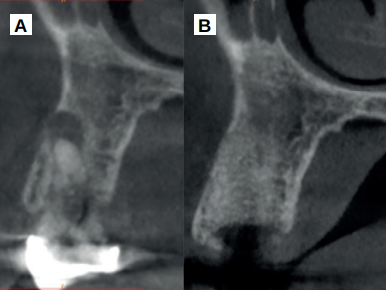

Caso clínico: se presenta el caso clínico de una mujer de 61 años, que acudió a consulta presentando dolor intenso en la zona del segundo premolar superior derecho (1.5). Se realizó la exodoncia del 1.5, usándose como diente donante para realizar una preservación del alveolo tras la extracción. Cuatro meses tras el procedimiento, se colocó un implante y se tomó una biopsia para realizar un análisis histomorfométrico. Un año tras la carga del implante se observaron buenos resultados clínicos y radiográficos.

Clinical case: a 61-year-old woman is presented, who came to private dental clinic presenting intense pain in the area of an upper bicuspid of the first quadrant (1.5). Exodontia of the 1.5 was performed, using it as a donor tooth to obtain the biomaterial to preserve its alveolus. After 4 months re-entry was performed and an implant was placed, harvesting a bone biopsy for histomorphometric analysis. One year post-loading, good clinical and radiographic results were shown.

El comportamiento clínico y radiográfico del diente autólogo ha sido demostrado en diferentes procedimientos de regeneración ósea guiada, elevación de seno maxilar y procedimientos de preservación alveolar12-16. En una reciente revisión sistemática, realizada en 202217, se ha demostrado que se trata de un material que consigue una mayor reducción de las dimensiones óseas cuando se emplea en preservación alveolar tras las extracciones y mejores resultados histomorfométricos en comparación con otros sustitutos óseos, como xenoinjertos y aloinjertos.